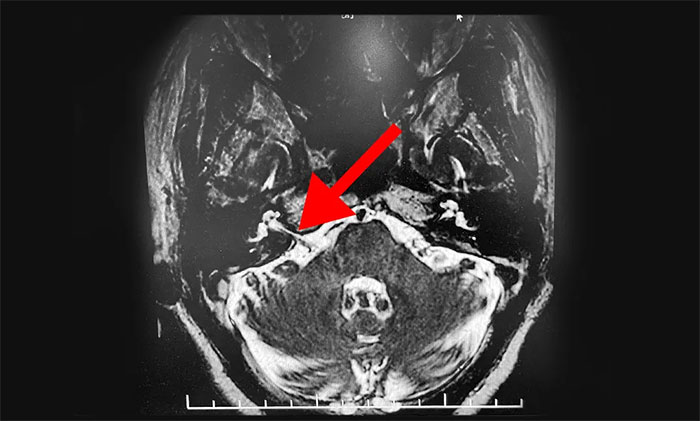

▲患者小腦血管與面神經(jīng)根關(guān)系密切

患者入院查體示,右側(cè)面肌陣發(fā)性不自主抽搐,右眼裂變小,口角向右歪斜,神經(jīng)系統(tǒng)檢查無其他異常。

頭顱磁共振檢查示,患者橋小腦角血管與面神經(jīng)根關(guān)系密切。結(jié)合患者病史及相關(guān)檢查,可明確診斷。